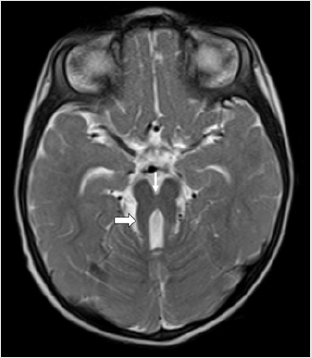

A 1-year-old boy presented to the Paediatrics department of our Institute with global developmental delay and extrapyramidal features. He was a term child born out of consanguineous marriage with an uneventful birth and family history. On examination, the infant was found to have nystagmus. No other ocular anomalies were present. No polydactyly or oro-facial defects were visualized. The patient was referred for MRI examination of brain in our Radiology Department which was carried out under sedation in Siemens Magnetom Aera 1.5 T MRI scanner. Axial MRI sections of brain revealed the characteristic “Molar Tooth” appearance of midbrain (Figure 1) with “Batwing Shaped” fourth ventricle. The cerebellar vermis was severely hypoplastic, dysmorphic and clefted (Figure 2). Sagittal MRI sections of brain showed small dysmorphic vermis with an elongated fourth ventricle. The roof of the fourth ventricle was convex upwards with an “enlarged rounded fastigial point”. Note was made of enlarged retro cerebellar space (Figure 3).

Figure 1: Axial T2 weighted (T2WI) MRI section of brain of a 1-year-old boy with global developmental delay and extrapyramidal features showing thickened superior cerebellar peduncles (thick arrow) and deep interpeduncular fossa (thin arrow) giving rise to the classical “Molar Tooth” sign of Mid brain. This sign is an obligatory imaging marker of Joubert Syndrome.

MRI is the primary imaging modality for diagnosis of Joubert Syndrome. “Molar tooth sign” is a mandatory and classical imaging feature seen on axial sections of brain. It is attributed to the malformation of midbrain and hindbrain where elongation and thickening of the superior cerebellar peduncles is seen along with a deep inter-peduncular fossa [1–3, 5]. Absence of decussation of fibres of superior cerebellar peduncles is the cause of deep interpeduncular fossa of mid brain. Using diffusion tensor imaging, this has been well illustrated via fibre tracking by Poretti et al [6]. Functional MRI has provided complementary information by recording abnormal activation patterns of brainstem nuclei. The other significant imaging feature of the disease includes “Clefted Vermis” with a “batwing Appearance” of Fourth ventricle. Midline sagittal sections of MRI show a small vermis which is dysmorphic with a deformed forth ventricle. The fourth ventricle is elongated, shows upward convexity of its roof and an enlarged rounded fastigium. Our case showed all these classical features of Joubert Syndrome on MRI imaging.Additional infratentorial manifestations include enlargement of the posterior cranial fossa, increased retrocerebellar CSF space along with hypoplastic as well as dysplastic cerebellar hemispheres.